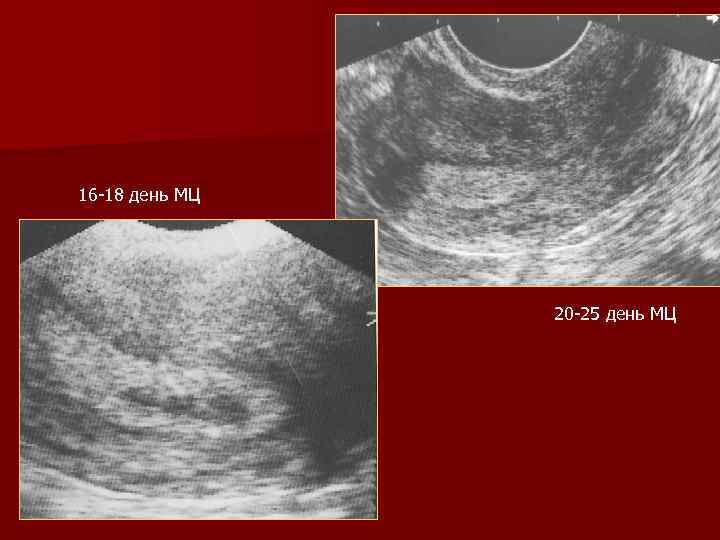

16 -18 день МЦ 20 -25 день МЦ

Вторая фаза менструального цикла Влияние прогестинов n Эндометрий гиперэхогенный n К 24 -27 дню толщина эндометрия постепенно снижается до 12 мм n